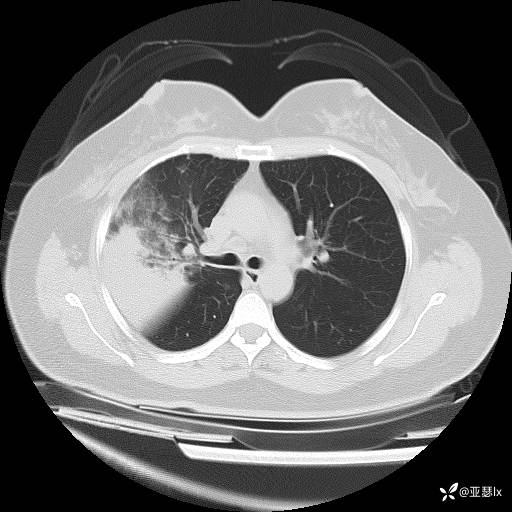

影像学:

初步治疗:经验性抗感染(左氧氟沙星+青霉素钾),同时筛查病原体。

治疗后复查影像学(2023.04.07)

患者体温有所改善,但影像学未见明显变化,后续行肺穿刺活检检查。